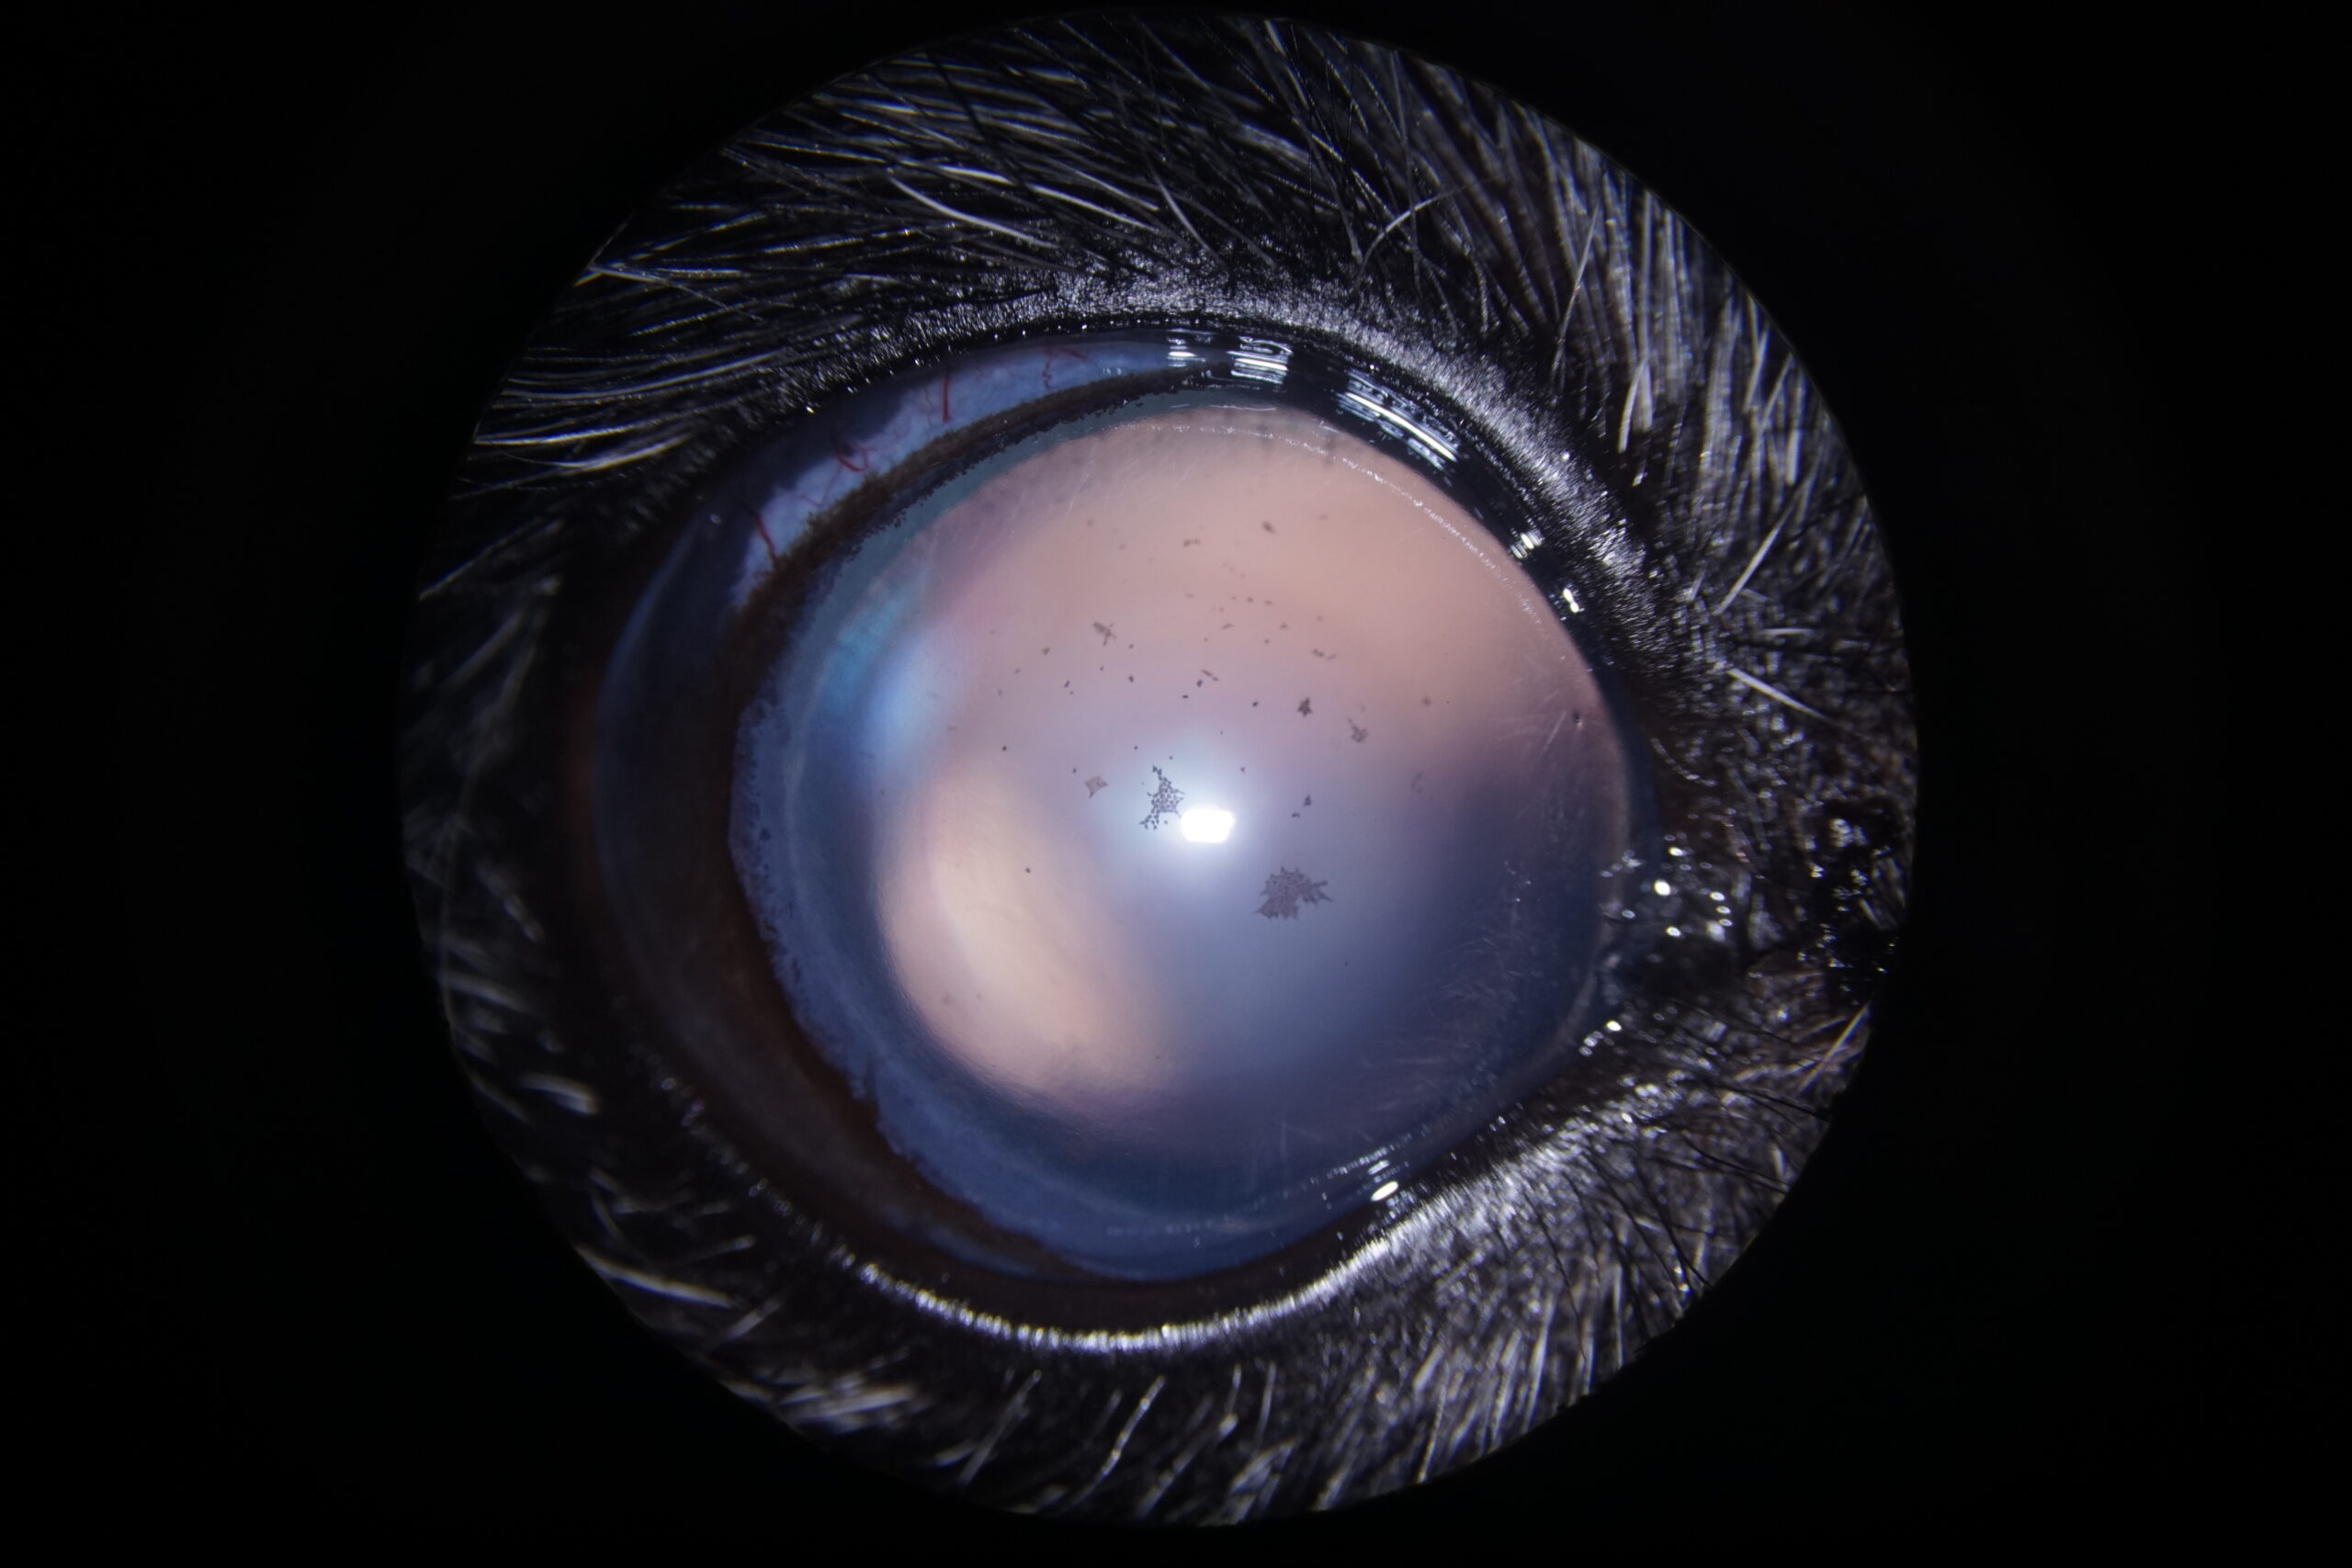

Un chien Cairn Terrier femelle de 10 ans a été présentée en consultation pour l’évaluation d’un glaucome évoluant depuis quelques semaines et ne répondant pas au traitement médical prescrit jusqu’alors (association d’un bétabloquant et d’un inhibiteur de l’anhydrase carbonique par voie locale). A l’examen, la vision a été considérée comme abolie avec absence de réponse à la menace et à l’éblouissement du côté droit. Les photographies 2a et 2b montrent l’aspect de l’œil au moment de la consultation. La photographie 2c est une vue gonioscopique de l’angle iridocornéen à travers une lentille de Koeppe de 17mm.

La pupille est dilatée et ne se contracte pas à la lumière, à tel point qu’il n’est pas visible sur la photographie. Des foyers pigmentés sont visibles sur la capsule antérieure du cristallin. La vue latérale montre un envahissement de la sclère par du pigment. La vue gonioscopique confirme la forte dilatation de la pupille. Les structures qui composent habituellement l’angle iridocornéen sont complètement désorganisées. Le ligament pectiné n’est plus visible et la fente ciliaire a été progressivement comblée par du pigment. Les procès ciliaires sont aussi épaissis et recouverts de pigment.